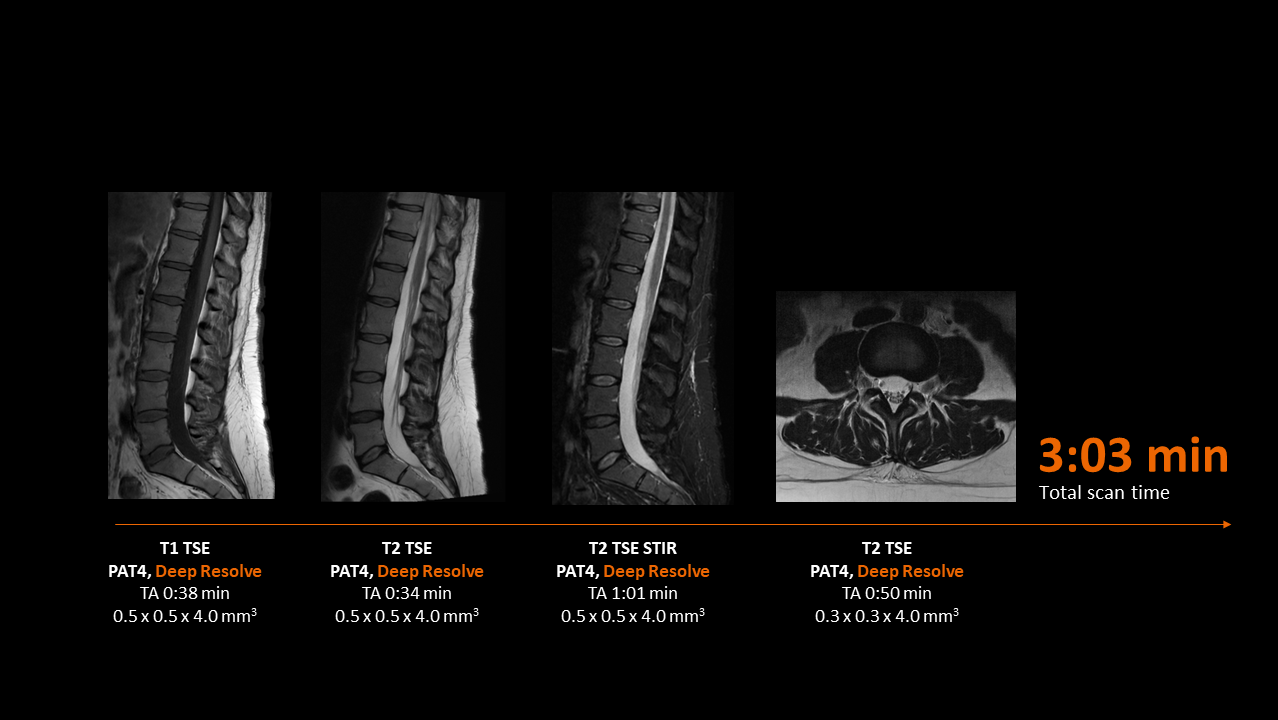

Deep Resolve will be at the forefront of the revolution in MRI acceleration. Deep Resolve will enable our fastest MRI, with images that will have extraordinary clarity, higher clinical productivity, and an even better patient experience. This transformational effect of Deep Resolve is now planned to expand to 3D5, unlocking a new dimension in MRI image resolution and speed.

More about Deep Resolve